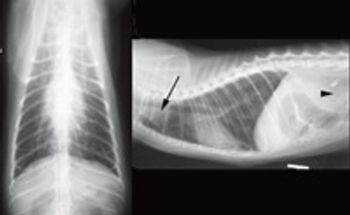

The goal of this article is to describe the common histologic variants, clinical signs, biologic behavior, and newest options for early diagnosis and effective treatment of primary lung tumors in dogs and cats.